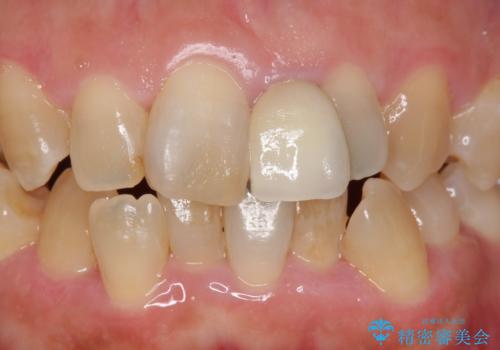

- 前歯の歯並びや色が気になるといらっしゃった方の症例です。

前歯4本をオールセラミッククラウンで補綴することで、歯の並びや色の改善を行いました。

今回用いたオールセラミッククラウンはジルコニアフレームという白い素材の上にセラミックを盛っているため、審美性が非常に高いのが特徴です。